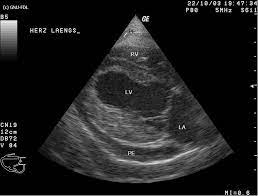

Häufig stellt der arzt dabei flüssigkeit zwischen herzmuskel und herzbeutel fest. Ein großteil der herzmuskelentzündungen geht mit nur leichten symptomen einher und heilt spontan wieder ab. Krankengeschichte (anamnese) und symptome ; Bei schweren formen einer herzmuskelentzündung folgt eine behandlung mit antiviralen medikamenten oder immunsuppressiva. Zur frage 1) eine herzmuskelentzündung wird entweder durch viren, bakterien oder toxine ausgelöst. Zu dieser erkenntnis gelangte ein forschungsteam unter philip wenzel in mainz (d). Sie entsteht oft infolge eines verschleppten, grippalen infekts. Sinnvoll ist dies auch bei einer herzmuskelentzündung. Zudem ist ihr gesamtes herz vergrößert und die. Einer herzmuskelentzündung geht oftmals ein grippaler infekt durch viren voraus und ist deshalb häufig sehr unauffällig. Diesen zustand nennen kardiologen perikarderguss. Gegebenenfalls ist auch das echokardiogramm in solchen situationen unauffällig. Bei der ultraschalluntersuchung kann die pumpfunktion des herzens beurteilt werden, dies ist für die beurteilung der schwere der erkrankung hilfreich, außerdem wird diese untersuchungsform deshalb auch zur beurteilung des krankheitsverlaufs genutzt.

Häufig stellt der arzt dabei flüssigkeit zwischen herzmuskel und herzbeutel fest. Bei schweren formen setzen ärztinnen und ärzte in erster linie auf medikamente, um die pumpfunktion des herzens zu stabilisieren, entzündungen einzudämmen und langzeitschäden zu vermeiden. Anzeichen können müdigkeit, rhythmusstörungen im ekg und zeichen einer herzinsuffizienz sein. Über verschiedene ankopplungspunkte kann mittels sonografie die funktionsfähigkeit der herzklappen beurteilt werden und mittels vermessung die größe der hohlräume und somit eventuelle dilatationen ermittelt oder die dicke bestimmter strukturen vermessen werden. Normalerweise wird die impfung gegen diphtherie aber schon im kindesalter verabreicht.

Während der untersuchung können sie wand, muskulatur, klappen und pumpleistung beurteilen. Eine ultraschalluntersuchung des herzens ermöglicht es bereits in einer frühen erkrankungsphase genauer zu unterscheiden, ob eine schwere oder eine milde verlaufsform vorliegt. Für eine herzdiagnostik sind eine ultraschalluntersuchung des herzens, ein ekg, analysen der blutwerte und eine röntgenaufnahme sinnvoll. Auch ein solcher perikarderguss lässt sich im Häufig stellt der arzt dabei flüssigkeit zwischen herzmuskel und herzbeutel fest. Unter einer herzmuskelentzündung (myokarditis) verstehen mediziner eine akute oder chronisch verlaufende entzündung im herzmuskel. Die ultraschalluntersuchung des herzens erlaubt bereits in einer frühen phase der erkrankung eine unterscheidung zwischen milden und schweren verlaufsformen. Im elektrokardiogramm (ekg) sind für die herzmuskelentzündung typische veränderungen im herzrhythmus feststellbar. Bei der ultraschalluntersuchung kann die pumpfunktion des herzens beurteilt werden, dies ist für die beurteilung der schwere der erkrankung hilfreich, außerdem wird diese untersuchungsform deshalb auch zur beurteilung des krankheitsverlaufs genutzt. Ein großteil der herzmuskelentzündungen geht mit nur leichten symptomen einher und heilt spontan wieder ab. In leichten fällen reicht körperliche schonung als therapie. Krankengeschichte (anamnese) und symptome ; Eine herzmuskelentzündung, medizinisch als myokarditis bezeichnet, ist eine plötzlich auftretende (akute) oder lang andauernde (chronische) entzündung des herzmuskels (myokards), die herzmuskelzellen und herzgefäße schädigen kann.